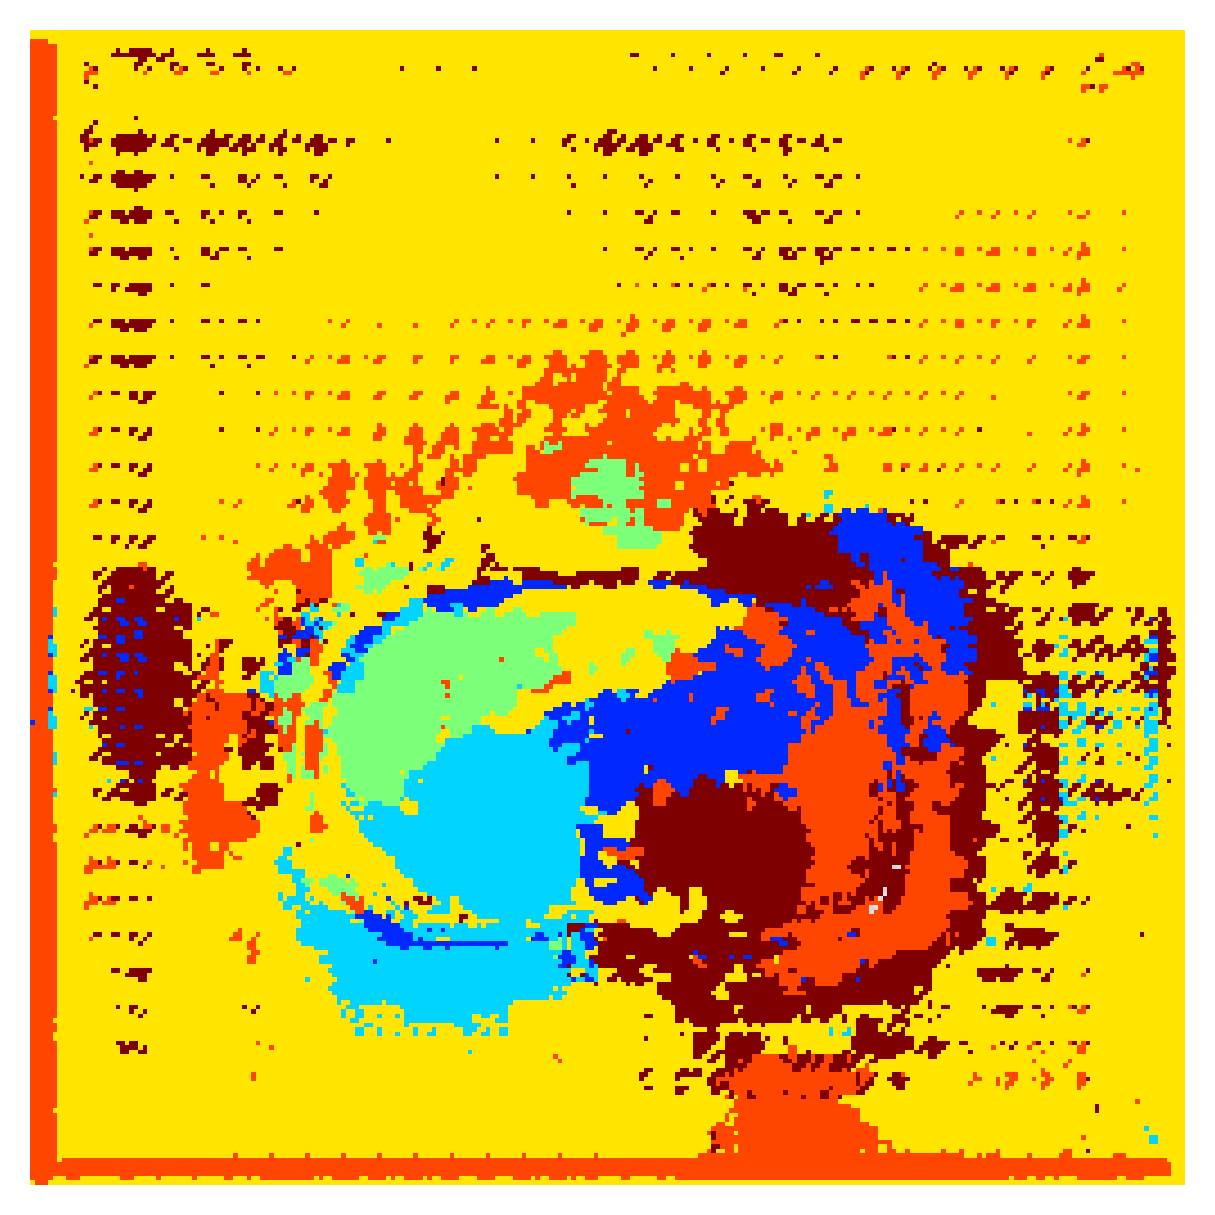

Generally, given an exact, full annotation of an object, such a Euclidean signed distance map encodes also information on the shape of an object. But when using a weak ground truth , where and , inferring a correct extent and shape of the objects is nontrivial. As shown in 1(b), Euclidean distance calculated from a point label source grows radially, regardless of the actual shape of the object, and thus makes little sense from an information point of view. Under the assumption of intra-object homogeneity and inter-object contrast (w.r.t intensities), this problem can be circumvented to a degree by using a distance function that takes also intensity values into account. An example of a commonly used distance measure with an intensity component is the Geodesic distance ([34]). Let denote a path between , with and being neighbors under a chosen adjacency relation. Reusing the notation from before, a Geodesic distance map from the boundary of the ground truth class , , can be defined as

While setting the parameter to actually results in a taxicab distance, which can be seen as a discrete approximation of a Euclidean distance, setting focuses purely on image intensities. We call the latter simply Intensity distance, . From here on we shall use the term Geodesic distance, , to denote the setting of , and Euclidean, , to denote the setting .

Both the Intensity and the Minimum barrier distance are defined exclusively on the image intensity space. However, from the examples of distance map in 1(d), we can notice that the values still increase somewhat radially from the annotation. This behaviour is similar to the one of the Geodesic distance in 1(c) (which actually includes the spatial proximity in its definition), and is due to the summing operator in the general Geodesic distance definition in Equation 3. While the intensities of two neighboring pixels on a path may be the same, that will rarely be the case in real life, noise riddled images. This makes the Intensity distance function approximately monotonically increasing with increasing length of the path (in space), even on paths where the intensity is mildly fluctuating (e.g. consider a path with even pixels intensity value of and odd pixels intensity value of ). One could thus argue that such a definition of a distance, despite being based exclusively on intensities, is still capable of loosely encoding the spatial distance information.

On the other hand, while we can see that the MBD based maps are similar to Geodesic and Intensity ones (1(e)) with respect to the object shape recovery, they have a less pronounced and smooth increase in the values outward from the source point.

In contrast to Euclidean distance, the Geodesic, Intensity and Minimum barrier distance maps all encode contrast sensitivity and preserve the object structures by harnessing the intensity information of the underlying image. This holds even when calculated from point sources. In practice, using such maps for network training could mean a lower penalty for false positives that occur farther from the point annotation but are close to it in intensity. Thus still enabling the propagation of a sort of shape information (as it can be inferred from the raw image intensities).